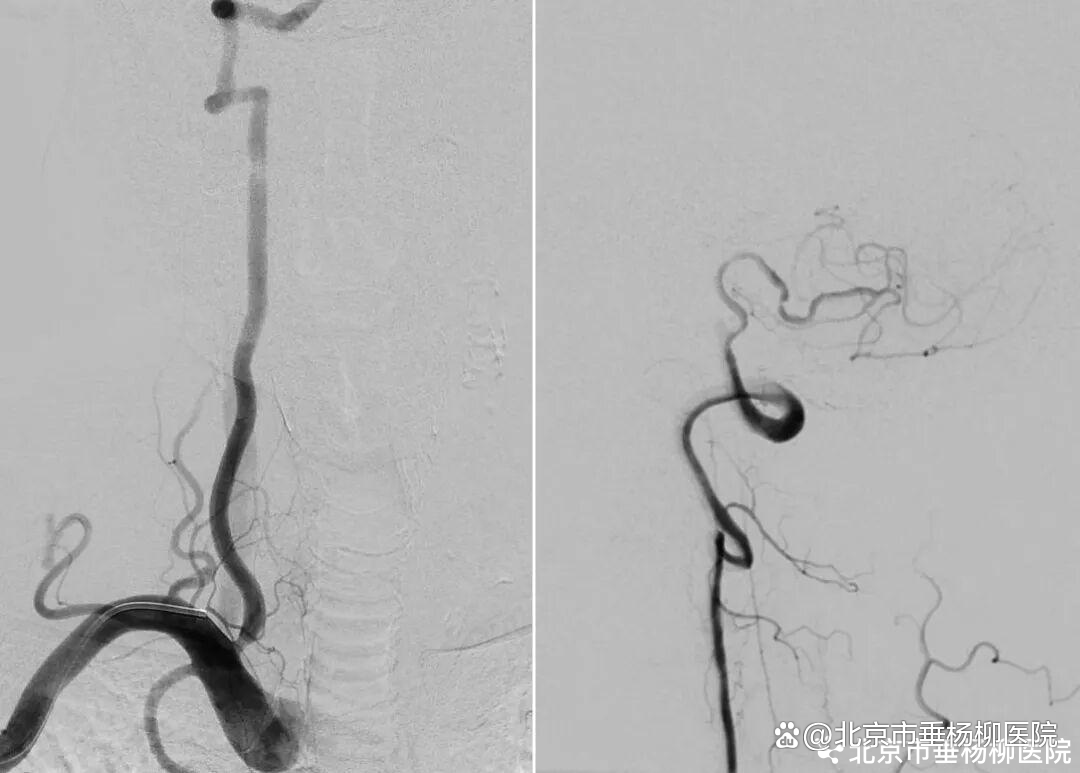

患者高先生,70岁,患有高血压病多年。2年前曾行冠状动脉搭桥术,平素规律服药。2个月前,他因左上肢突然麻木被送至清华大学垂杨柳医院急诊科就诊。头颅CT提示右侧顶叶少量蛛网膜下腔出血。后入住神经外科进一步诊治,全脑血管造影(DSA)结果显示:右侧椎动脉起始部重度狭窄约70%,左侧椎动脉颅内段闭塞;右侧椎动脉颅内段存在大小约3.5×2毫米的夹层动脉瘤;右侧颈内动脉颅外段存在重度狭窄,左侧颈内动脉通过前交通动脉代偿。

▲右侧椎动脉起始重度狭窄,左侧椎动脉颅内段闭塞